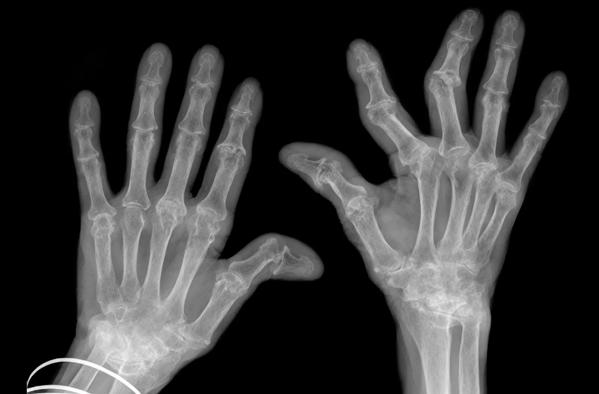

hand xrays showing advanced rheumatoid arthritis